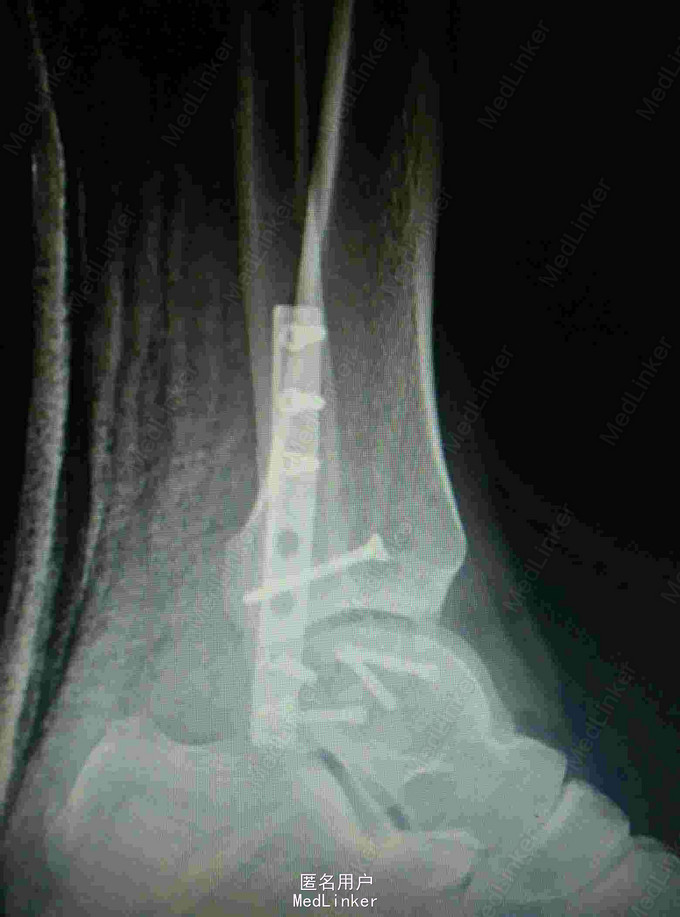

行外踝截骨入路显露复位螺钉固定术

术后功能好,体表像,复查X线片